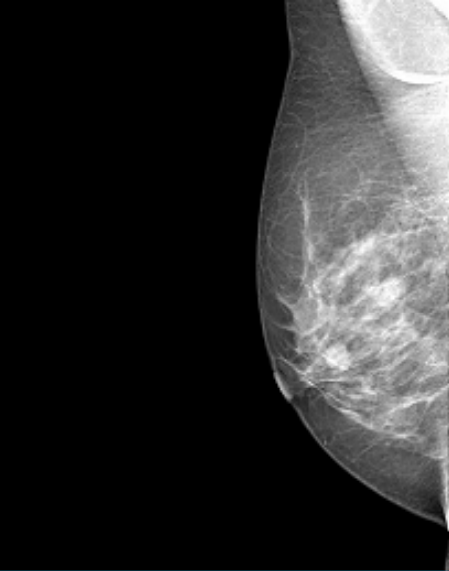

Datos Clínicos: Paciente Femenino de 54 años.

Diagnóstico: Calcificación Probablemente Benigna.

Formatos disponibles de la imagen: DICOM.

Dimensiones: 632 x 548.